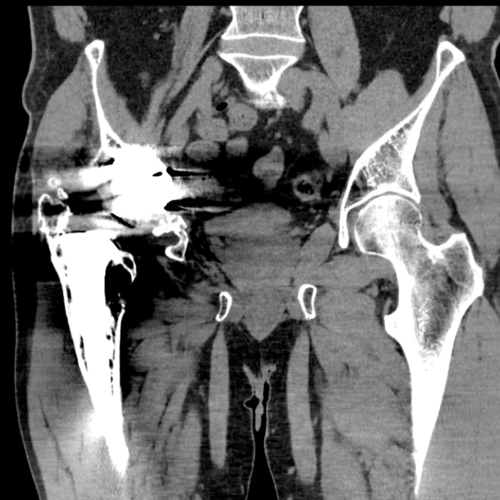

Imaging revealed anterior and medial wall deficiencies with a raised centre of rotation. The posterior column remains intact.

The pre-operative cross sectional imaging demonstrates the extent of the intrapelvic migration